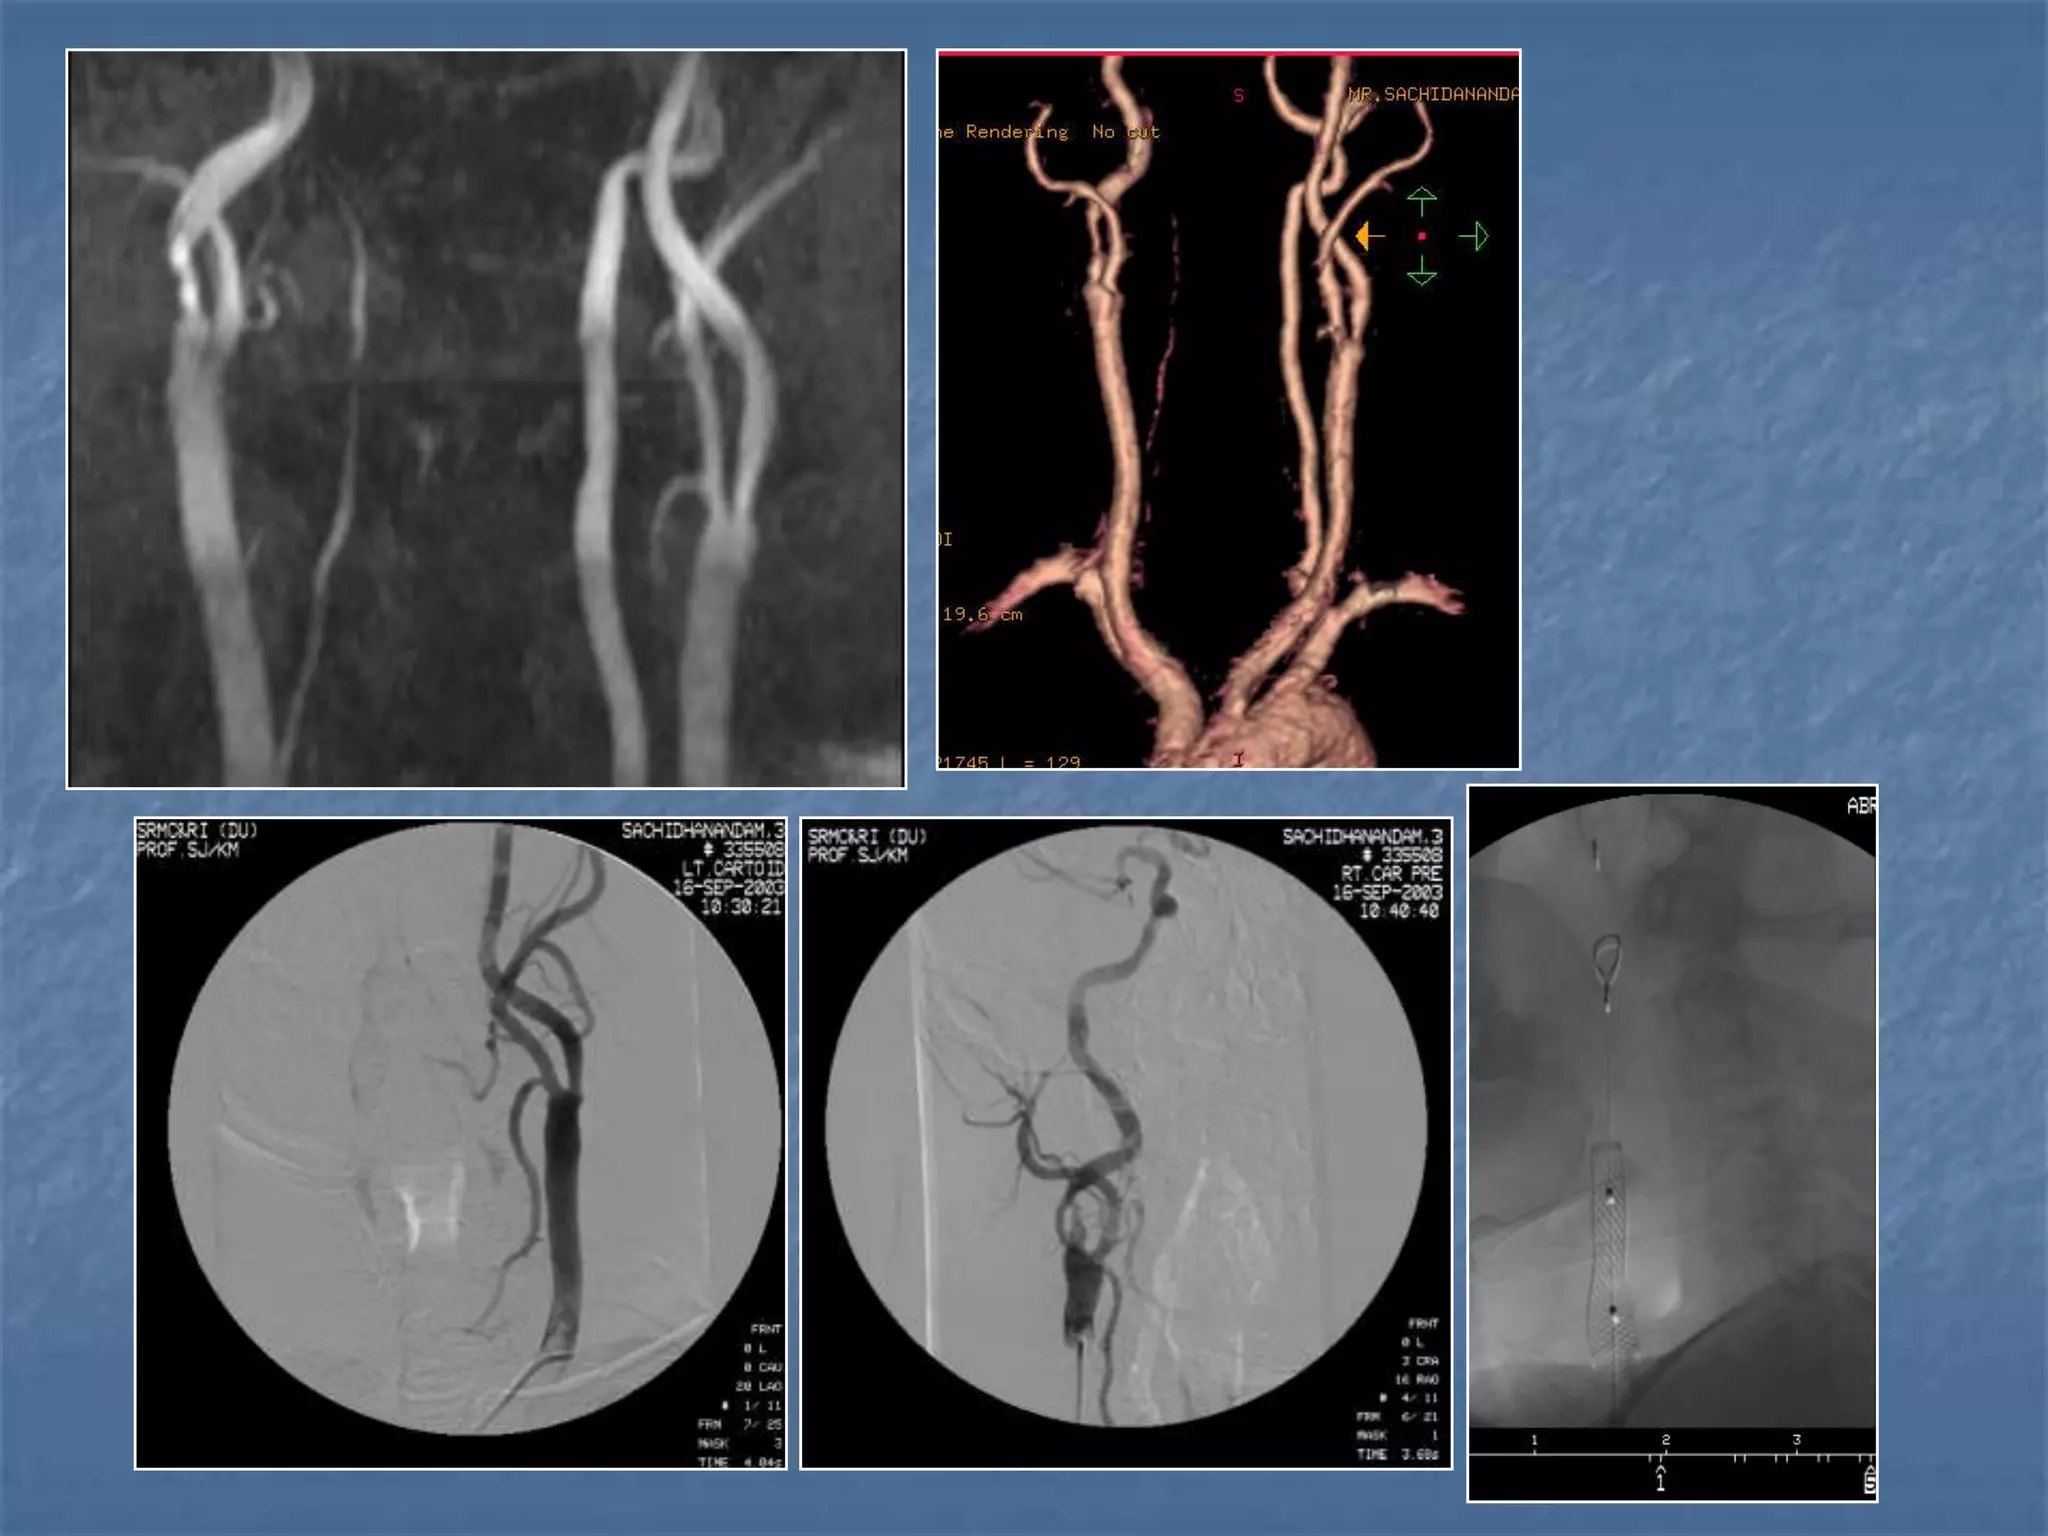

CT Angiography

 Site of occlusion

 Length of occluded

segment

 Arteries beyond occluded

segment – collateral flow

 Detection & exclusion of

large vessel intracranial

occlusion – sens – 98.4%

and spec.-98.1%

JCAT 2001; 25(4):520-8